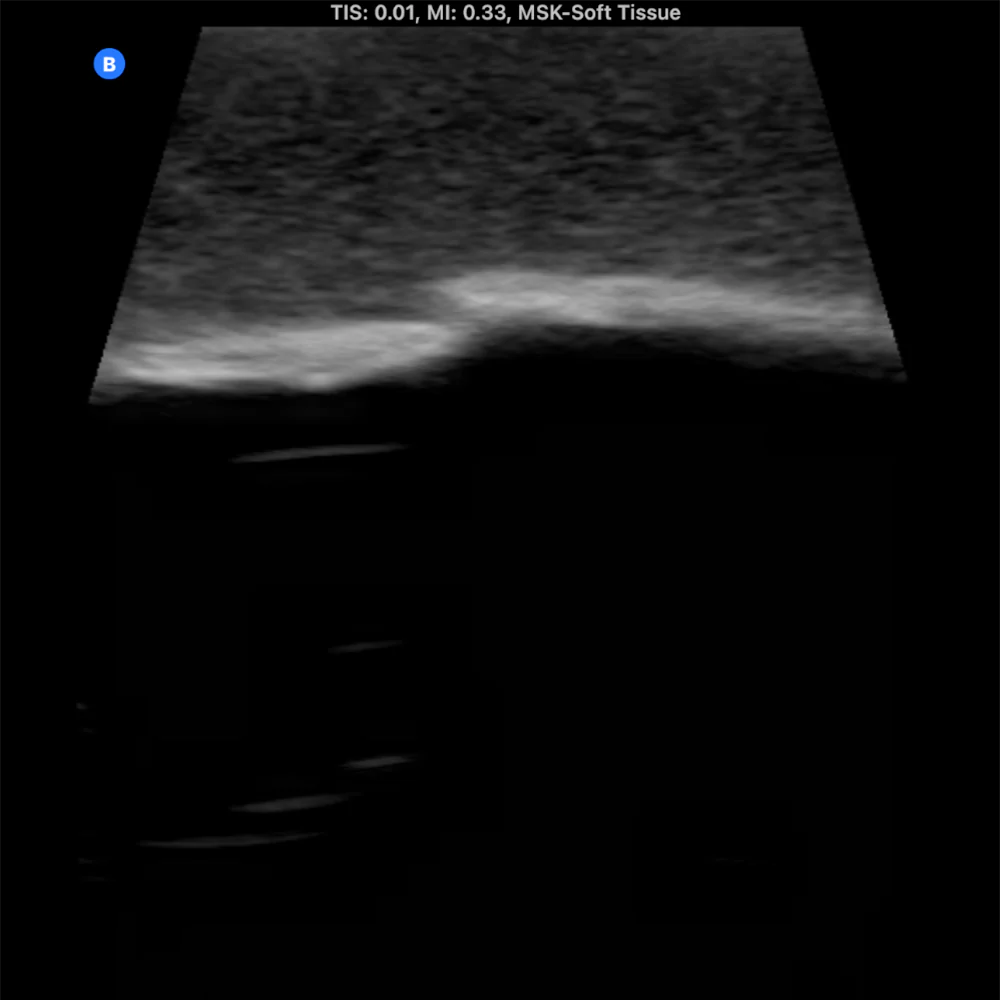

The Bone Fracture Ultrasound Phantom is an excellent training aid for developing the skills needed to identify bone fractures within soft tissue.

- Five bones incorporated within the model (three positioned superficially and two at a deeper level).

- One healthy bone with no fracture, plus four bones featuring fractures of varying severity.

- Produces outstanding ultrasound image quality.